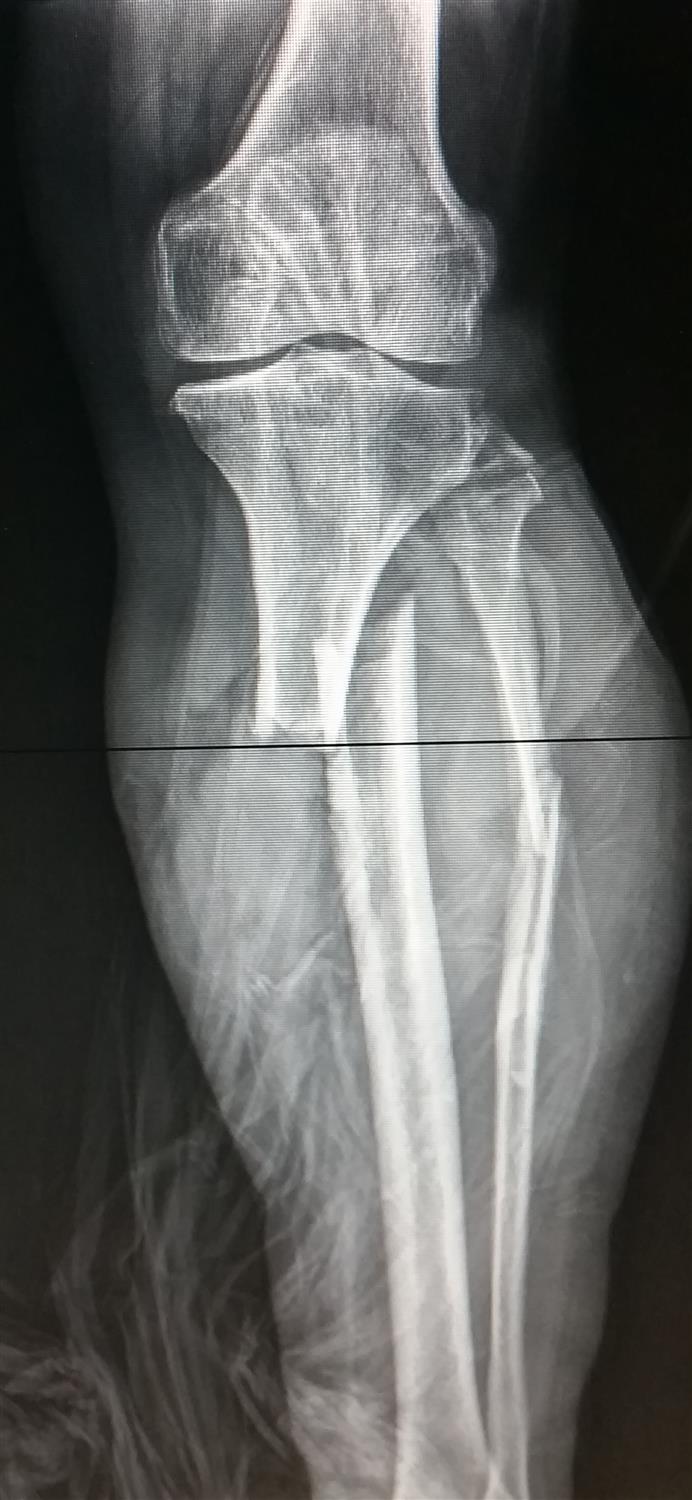

THA Periprosthetic Fracture Recon Orthobullets

from www.orthobullets.com